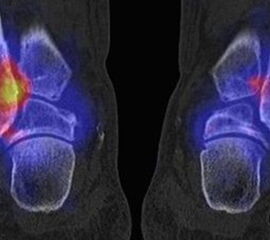

Abbildung 2.1.

Bildbeispiele symptomatische OCL

Zum Lesen der Bildbeschreibung und zur Vollansicht bitte das Bild anklicken. Bild: H. C. Rischke

Abbildung 2.2.

Bilder eines Patienten mit Z. n. mehrfachen Sprunggelenksdistorsionen in der Vergangenheit, besonders heftige Distorsion des linken Sprunggelenkes 5 Wochen vor der Untersuchung. Die SPECT/CT zeigt eine instabile osteochondrale Läsion mit deutlicher Aktivierung.